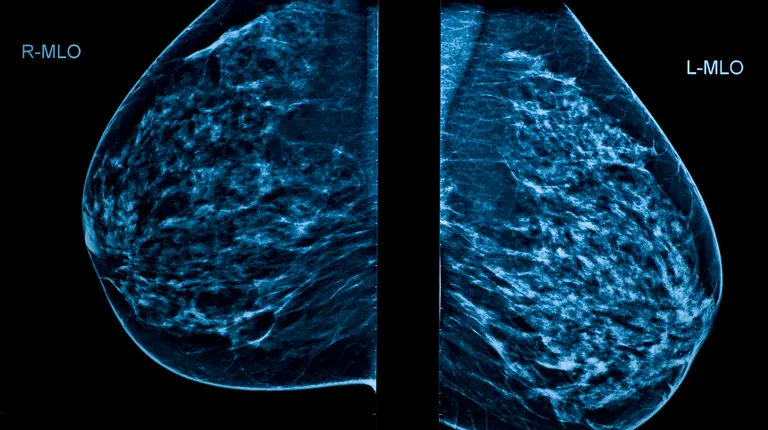

Avec le soutien financier du Programme d’aide à la recherche industrielle du Conseil national de recherches du Canada (PARI CNRC), Mila a fourni des services de consultation à plus de 40 PME canadiennes innovantes travaillant sur des projets d’apprentissage automatique appliqué. Ces collaborations permettent aux entreprises d’intégrer avec succès l’apprentissage automatique dans leurs opérations, de renforcer leurs capacités internes et de faire progresser leur parcours d’innovation. Par exemple, Densitas, basé à Halifax, et Mila ont collaboré à la création d’une solution d’IA pour améliorer le dépistage du cancer du sein et faire progresser la technologie au service de la santé des femmes. Pendant ce temps, Metareal, basé à Magog, a travaillé avec Mila pour développer un modèle de type Vision Transformer (ViT) qui rectifie automatiquement l’alignement des images dans les visites virtuelles en 3D, permettant à l’entreprise de lancer son premier produit basé sur l’IA.

Image de mammographie montrant les seins gauche et droit.